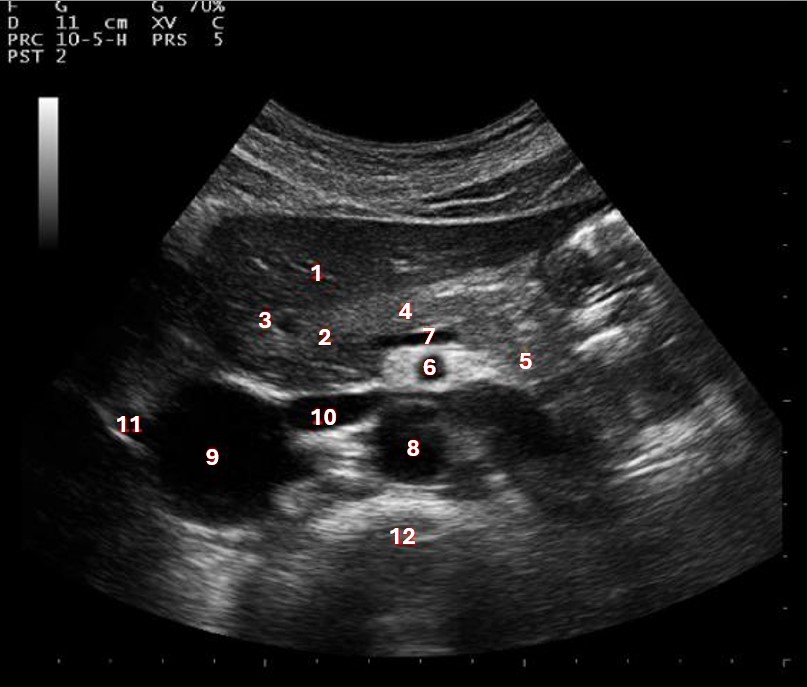

What structure/vessel is indicated by #3?

Gastroduodenal artery

What structure/vessel is indicated by #2?

Head of pancreas

What structure/vessel is indicated by #1?

Medial branch of LPV

The yellow arrow on the image represents which of the following structures?

Caudate lobe

What structure/vessel is indicated by #6?

Superior mesenteric artery

Left portal vein

What structures last vessel is indicated by #4?

Medial left lobe

What structures/vessel is indicated by #5?

Tail of the pancreas

What structure/vessel is indicated by #12?

Spine

Which structure/vessel is indicated by #4?

Body of the pancreas

Lateral branch of LPV

What structure/vessel is indicated by #7?

Splenic vein